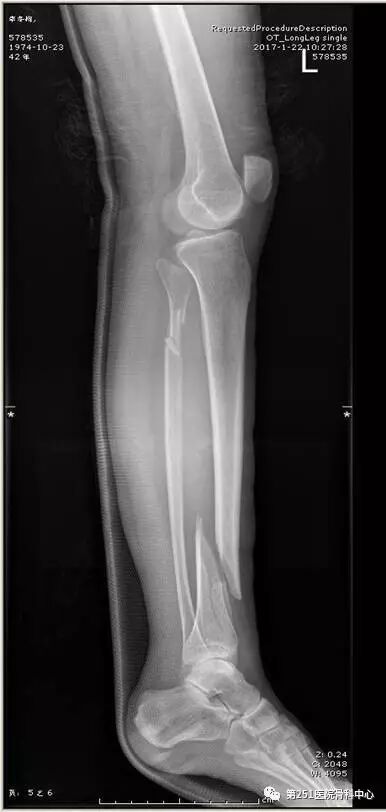

病例2:男性,44岁,车祸伤,双侧胫腓骨骨折(左侧)。